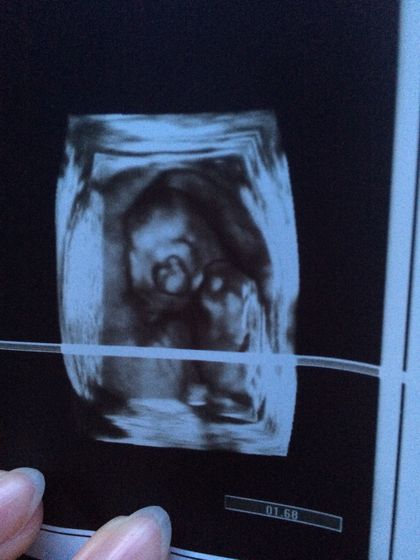

16 недель . Определение пола . 25 минут высматривали , живот мяли) пуповина была между ног )) и вот спустя 25 минута показал нам своё сокровище - мальчик !!!

Как будто во рту соска))

Ручкой за ухо держит )))

Мне 6 штук сделали. Для меня там только парочку понятных )) тут ручкой за ухо держит )